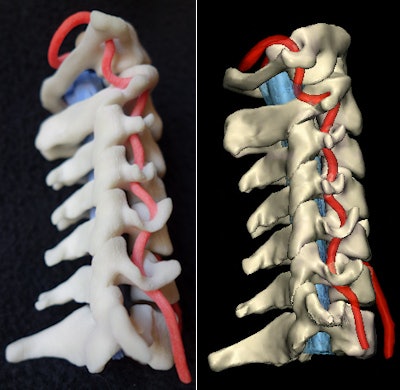

3D printing of internal anatomical structures

Last year was the first time 3D printing made the list of Minnies candidates, and one year later the technology is already a finalist for Hottest Clinical Procedure.

The stunning rise of 3D printing in the Minnies parallels how quickly the phenomenon has taken over healthcare, both in radiology and in other medical specialties. Some market projections predict that 3D printing in healthcare will be worth more than $2 billion by 2020 -- a mere four years away.

3D printing offers the promise of custom-printed structures such as orthopedic implants that are tailored to the recipient's anatomy, as well as the ability to better plan surgeries by printing organs that surgeons can manipulate and interrogate in advance. Medical imaging is the critical foundation of 3D printing, acquiring the data necessary to create such anatomically precise models.